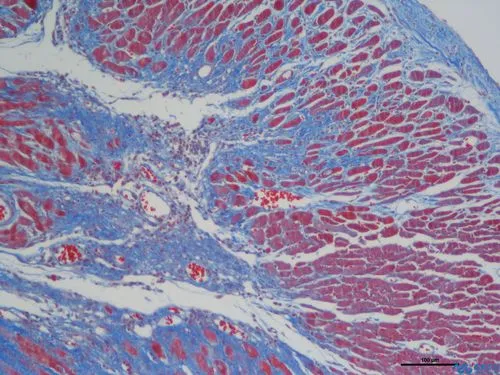

完成以上步驟后,切片中的膠原纖維、黏液和軟骨將呈現(xiàn)藍色(如果使用淺綠色液體,則呈現(xiàn)綠色),細胞質(zhì)、肌肉、纖維素和神經(jīng)膠質(zhì)將呈現(xiàn)紅色,而細胞核將呈現(xiàn)黑色和藍色。